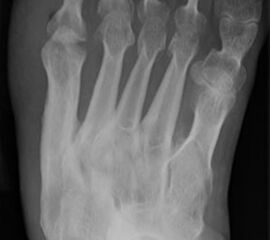

Abb. 3a, b: Präoperatives (a) und postoperatives (b) Röntgenbild bei Korrektur einer Typ I Deformität durch eine Exostosenabtragung.